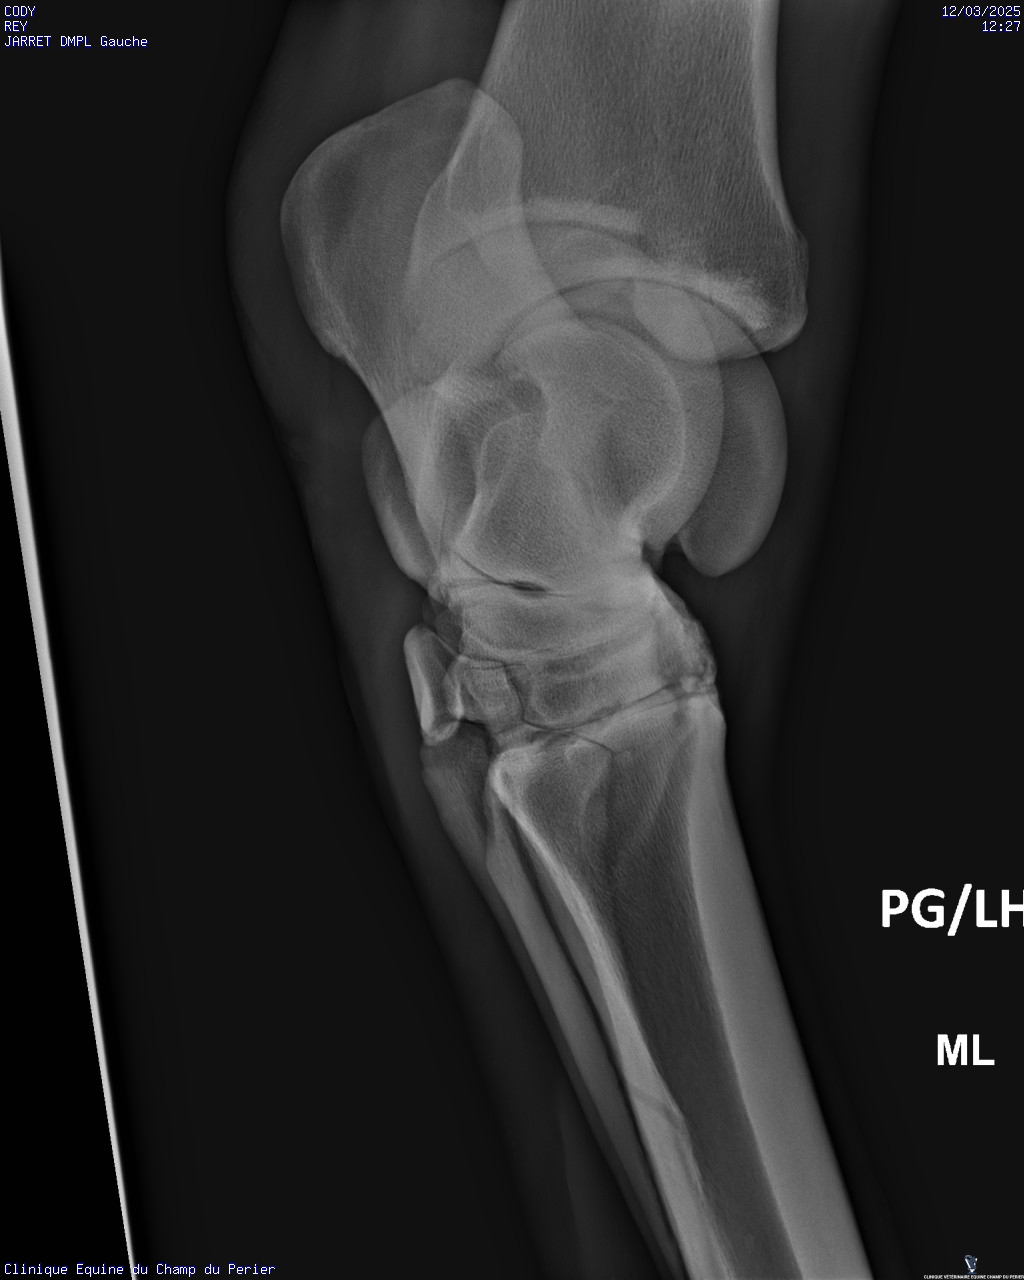

| Dire merci | Voici les résultats : - pieds antérieurs : novembre 2024 : perte de parallélisme entre les 3° phalanges des deux antérieurs et les sabots-parois dorsales ; pieds trop longs en pinces - pieds postérieurs ce jour : très léger défaut de parallélisme entre P3 et parois dorsales des sabots, mais pinces trop longues. Un défaut en phase de correction sou le sabot PG, en ponte de fourchette. On note aussi un ostéophyte au sommet dorsal de P2 sur le PD. - jarrets : on note sclérose des os centraux et troisièmes os des tarses + lyse forte de ces deux os sur le jarret gauche Ccl : comme indiqué sur mon ordonnance il faut : - parer les sabots afin d’obtenir au fur et à mesure le parallélisme entre les 3° phalange et les parois dorsales des sabots ; parer les pinces des sabots au plus court - poser des fers qui seront bien reculés et donneront de la surface d’appui en talons, sur les deux antérieurs - soulager la douleur pour les deux mois à venir avec Equioxx° un comprimé par jour. Le contrôle des enzymes rénales – normales – fait se jour le permet. - traiter CODY avec des biphosphonates (Osphos°, voire Tildren°) |

| Dire merci | C'est quoi une forte lyse ? C'est ça qui lui avait fait gonflé le jarret ? Finalement pas de fourbure ? (Tant mieux) (Et pour les anomalies que tu avais entouré en bleu sur les anciennes radio ? Il a dit quelque chose de spécial ?) |

| Dire merci | C'est pas une perte d os un peu comme l'osteoporose? Et donc un.machin lié à arthrose? Un veto pour expliquer? Message édité le 12/03/25 à 21:18 |

| Dire merci | Oui l’ostéolyse c’est la destruction du tissu osseux. Mais il n’avait jamais eu de radios du jarret G dans les multiples examens déjà faits? Parce que c’est vraiment pas beau là ![]() |

| Dire merci | Mais il n’avait jamais eu de radios du jarret G dans les multiples examens déjà faits? Parce que c’est vraiment pas beau là Je suis d'accord avec toi Juliie . Je ne voulais pas intervenir directement après le post des radios pour ne pas être la rabat-joie. Mais c'est pas job job au niveau des articulations (toutes les articulations en fait). Enfin le véto a dû te le dire. Quand ils préconisent du Tildren c'est que c'est déjà sérieux et bien avancé (en gros, le Tildren essaye de "bloquer" l'articulation en l'état pour ne pas que ça se dégrade davantage et je crois qu'il a aussi une action antalgique). Il a quel âge ton cheval ? Message édité le 12/03/25 à 23:45 Message édité le 12/03/25 à 23:45 |

| Dire merci | L'état du jarret gauche n'est pas bon. Il n'y a jamais eu de radios de faites, les différents pros m'ont dit que c'était sa conformation. J'ai dû insister pour faire les radios. Avec mon véto habituel on va programmer un tildren assez rapidement. Cody va prendre 11 ans cette année. De ce que j'ai compris les antérieurs douloureux font qu'il y a un report du poids sur les postérieurs. La priorité est de soulager la sensibilité des antérieurs, pas de chance le maréchal-ferrant s'est trompé de taille de fers, le ferrage est reporté de 10 jours. En attendant je dois donner un cachet d'equiox par jour. |